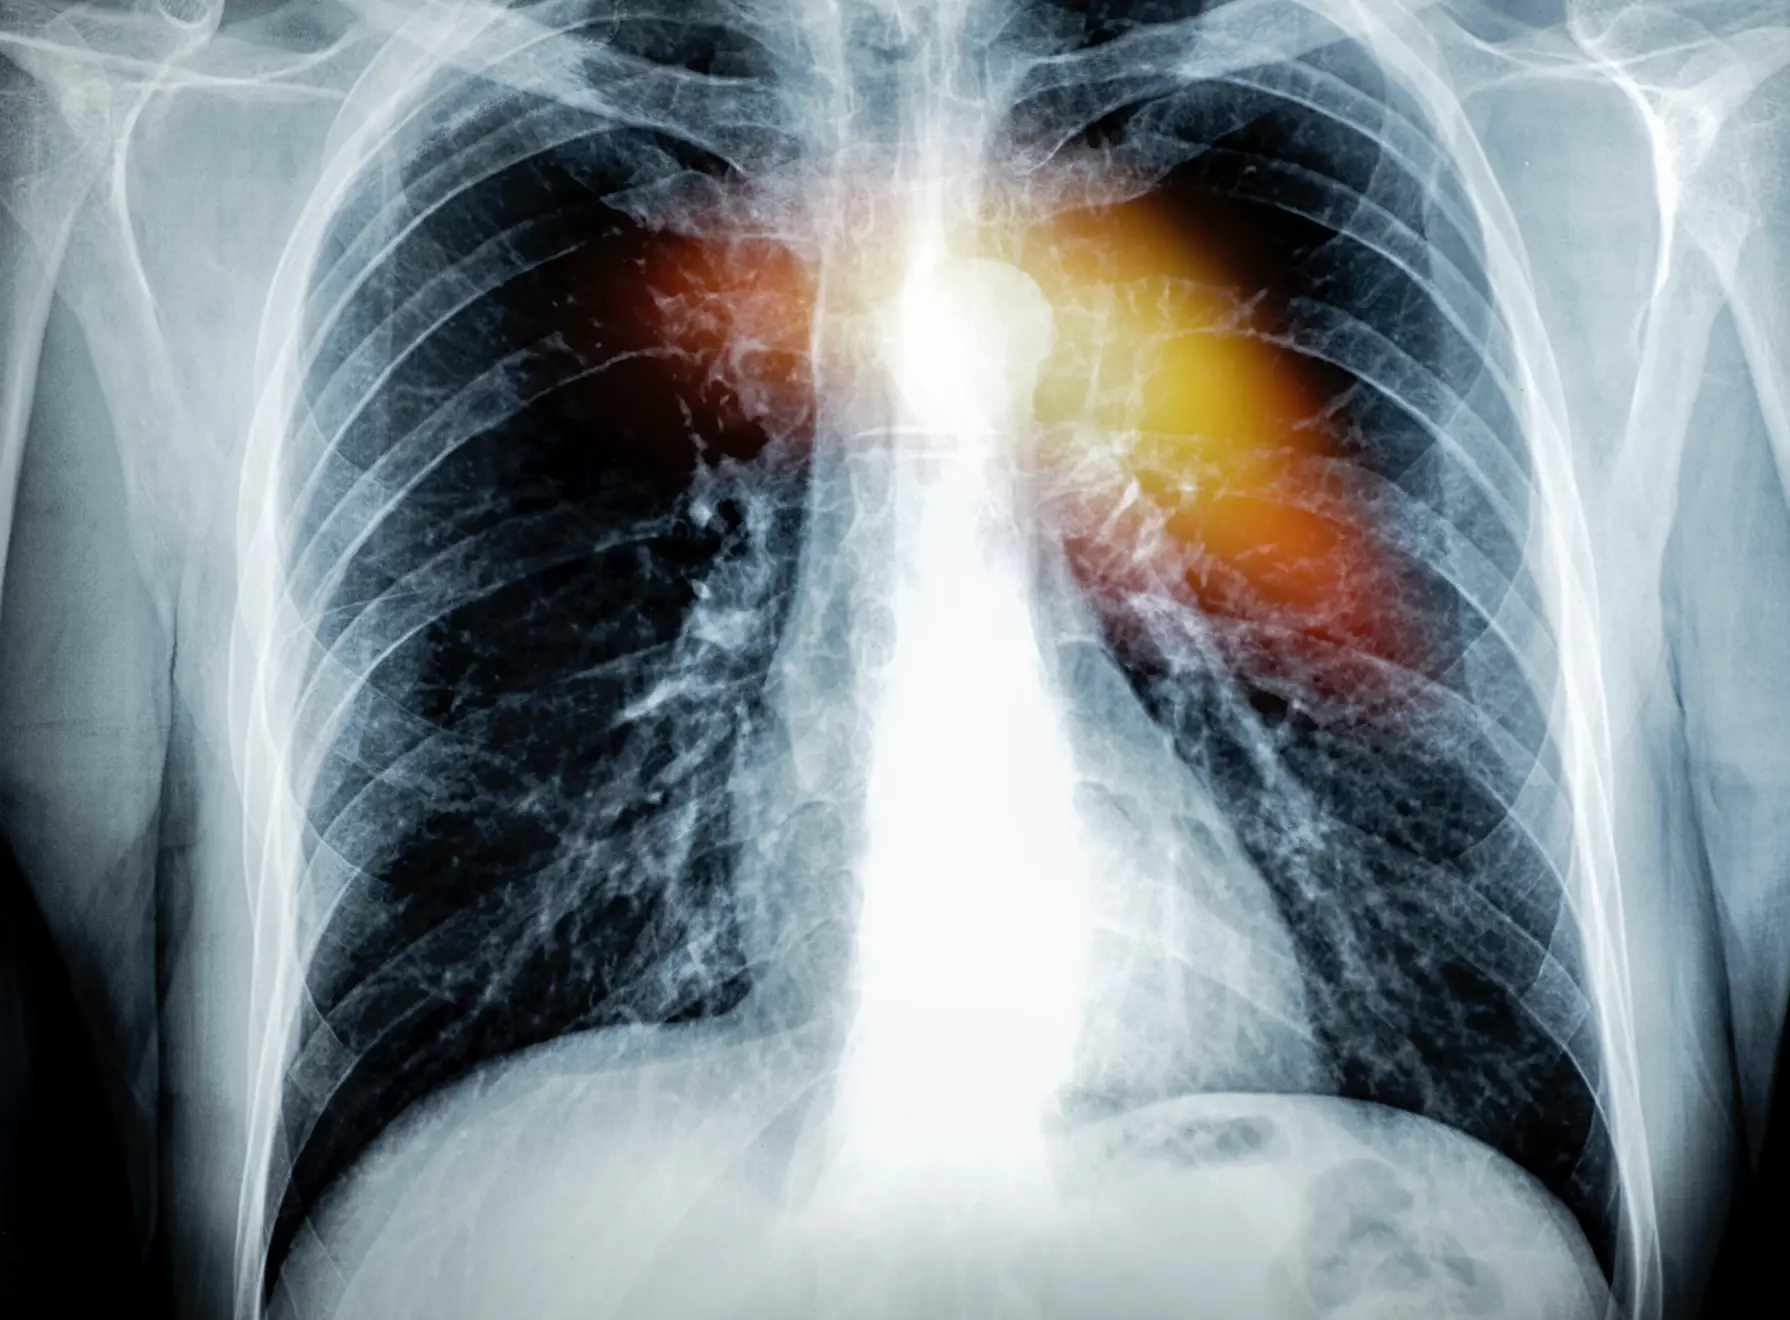

Both conditions are still caused by blockages of the blood flow to a section of the heart, which, in turn, causes scarring and damage to the heart muscle.

However, in cases of a 'silent heart attack', the flow of blood is caused by a build-up of plaque in the coronary arteries.